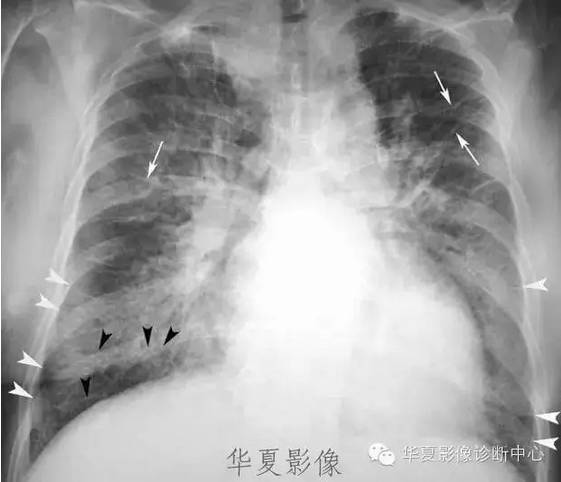

图 3 全胸片示心影增大,典型「蝴蝶影」,双侧肋膈角钝模糊,提示心衰

以双侧肺门为中心对称分布的大片状致密影,肺门区密度较高,边缘模糊